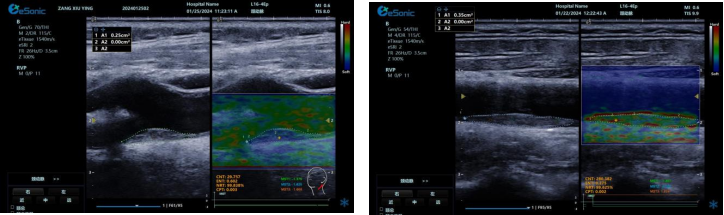

QPWV 彩色脉搏波传导速度定量技术

QPWV 技术是百乐博平台医疗的极速脉搏波速度测量技术,对脑卒中诊疗优势明显:

image.png

? 可进行动脉壁运动速度 - 时间彩色成像,直接测量单点脉搏波传导速度及相关参数(如 BSES 时的速度及标准差)。

? 能在血管内中膜增厚前的内皮功能不全阶段检测异常,对早期动脉硬化评估极具临床价值。

? 操作简单直接,无需附加设备,影响因素少,检测快速、重复性和稳定性高。